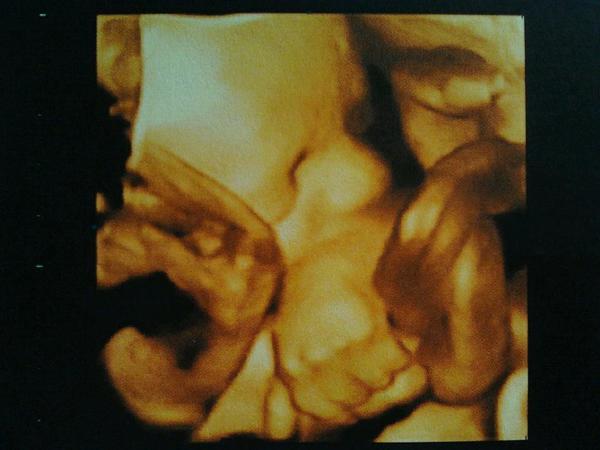

Насмотрелись на нашего кроху

, получили заключение с параметрами, фотографии и диск. Всё удовольствие 2400 р.